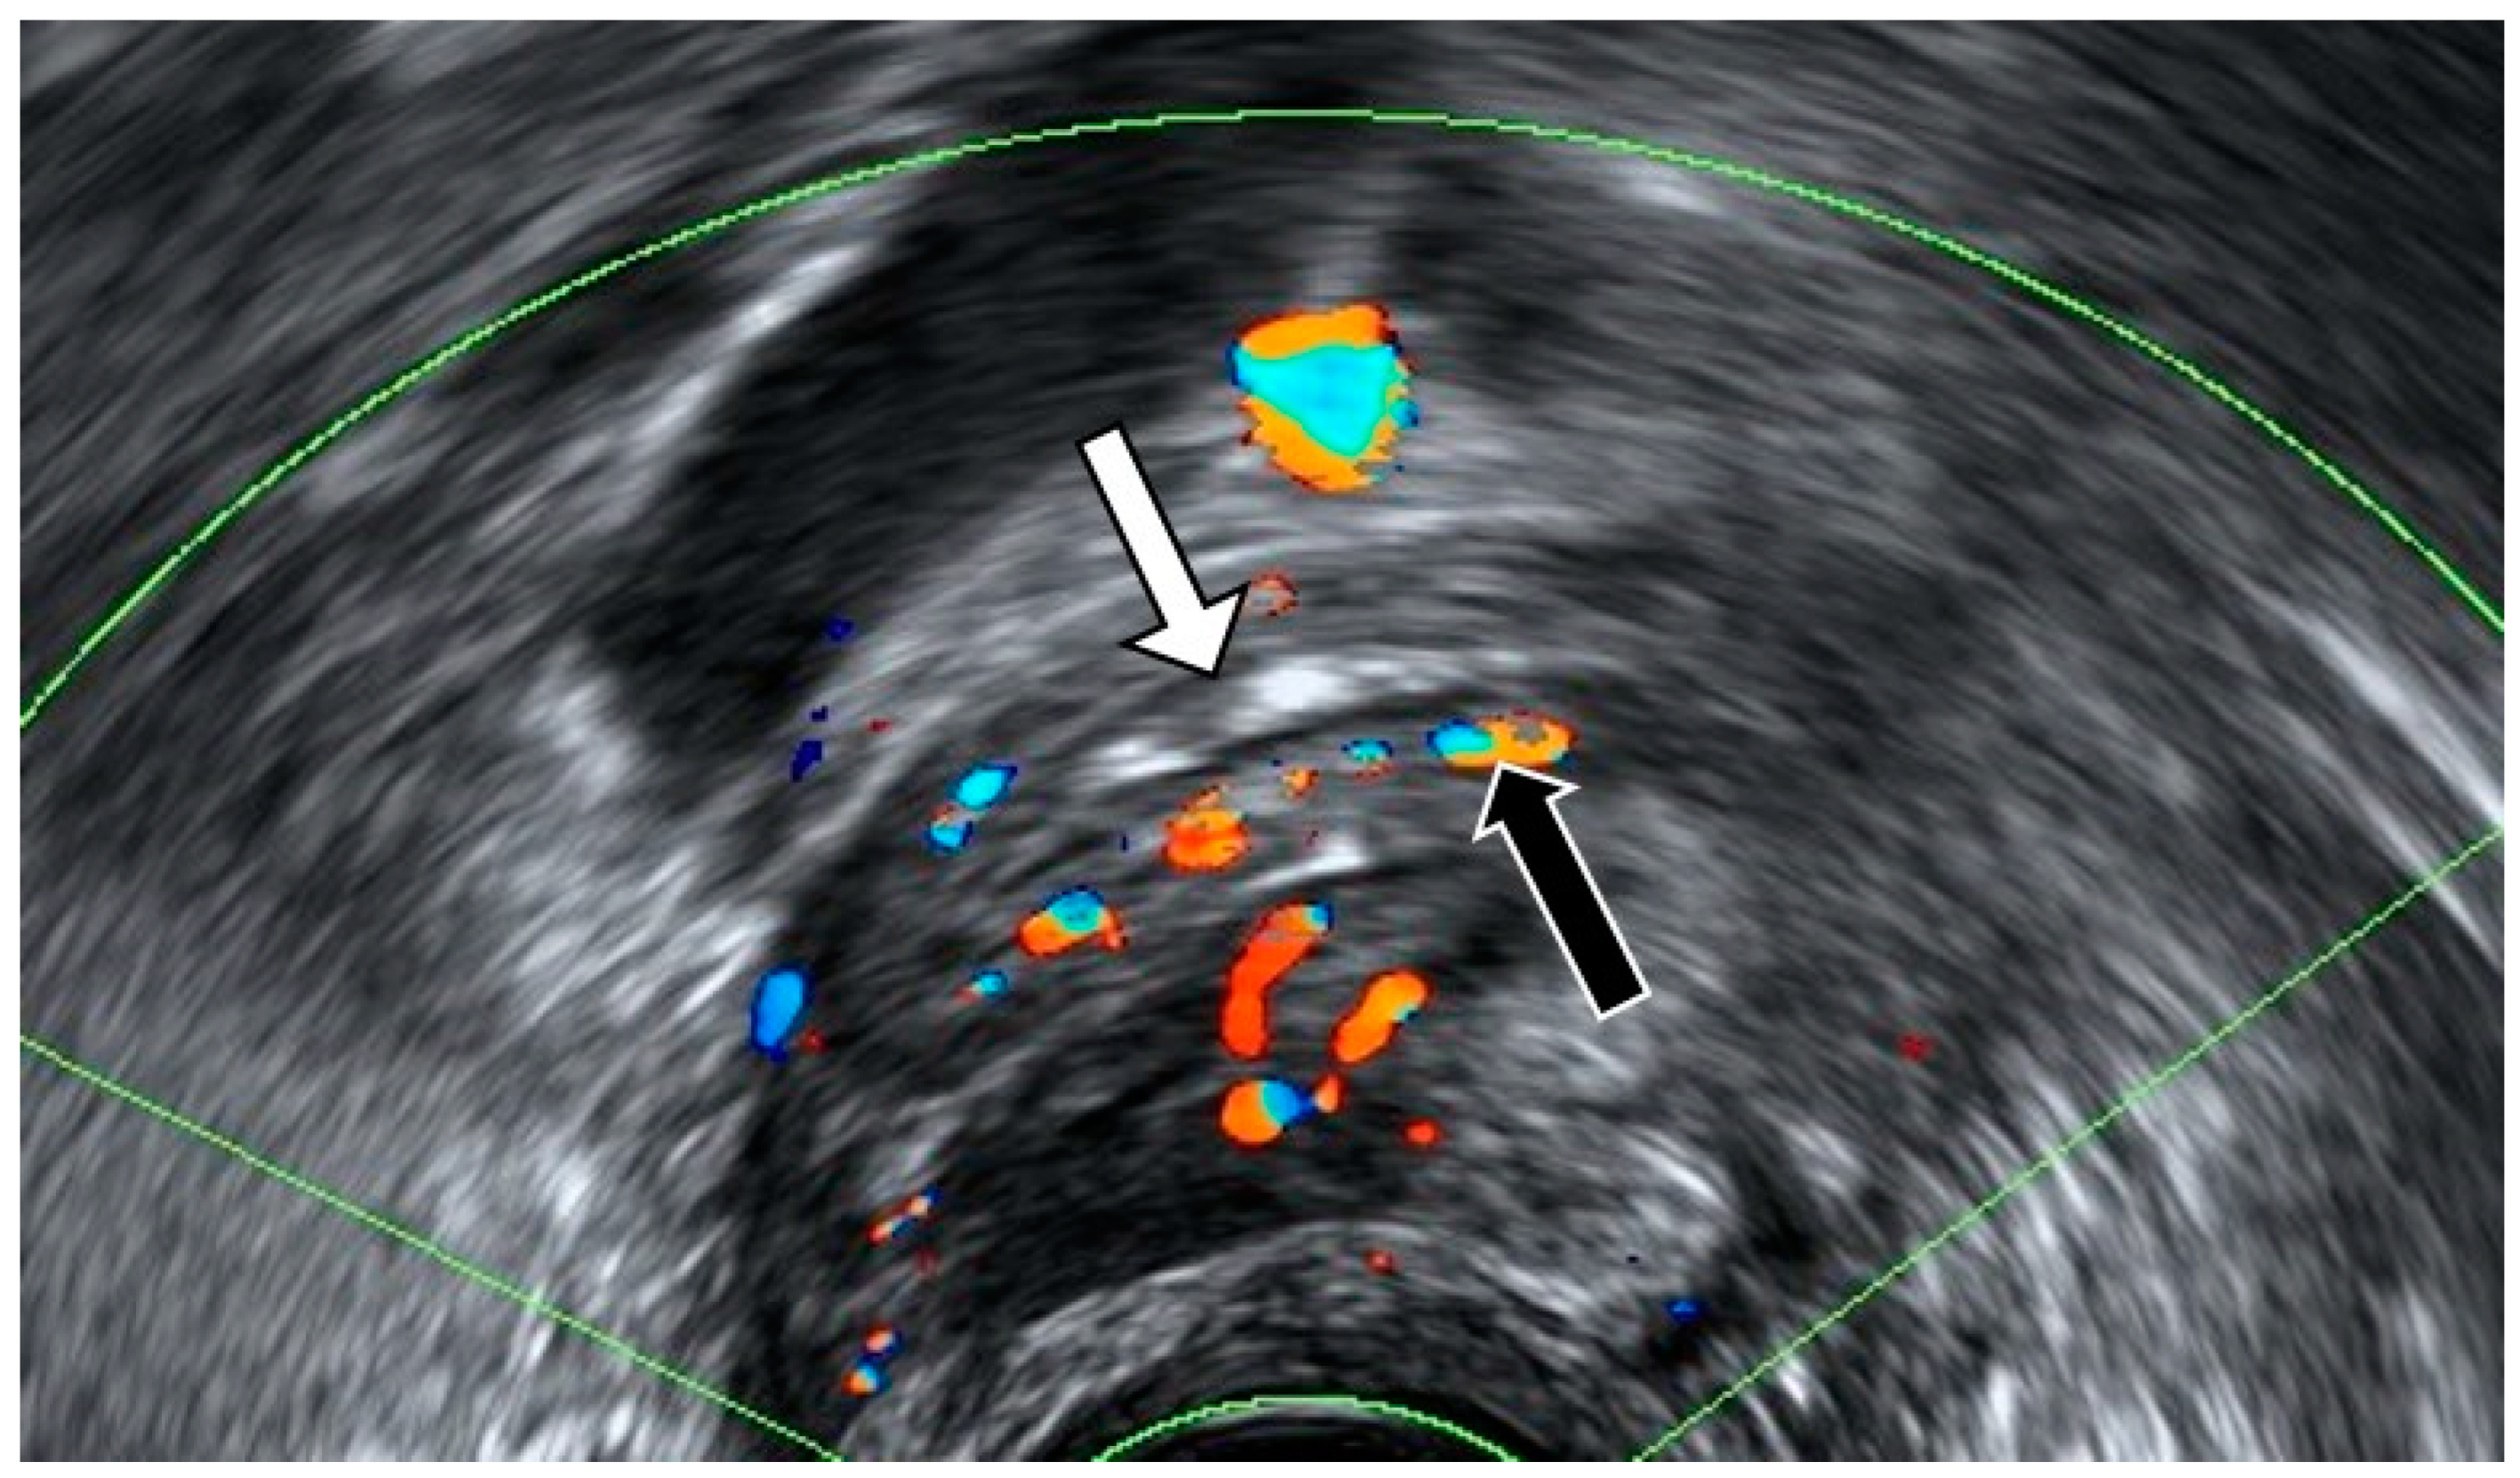

4.1. Pelvic Congestion